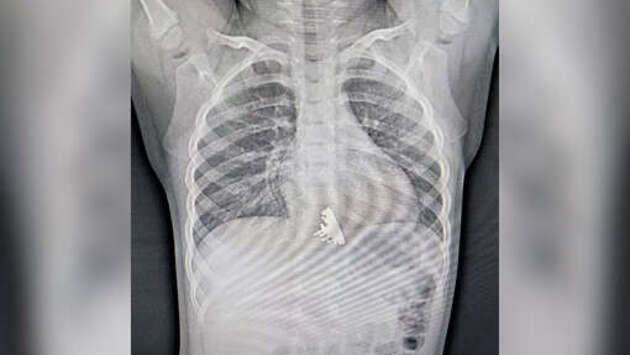

В Иркутске врачи достали из ребенка крейсер "Аврора", проглоченный во время игры. Об этом во "ВКонтакте" сообщает Ивано-Матренинская детская клиническая больница. Сообщается, что двухлетняя девочка проглотила крейсер, когда играла с конструктором. Ее родители заметили, что ребенок поперхнулся, стал подкашливать и беспокоиться. Они решили обратиться в больницу. Ребенку провели рентген, по результатам которого стало ясно, что у девочки в нижней трети пищевода находится инородное тело. Врачи приняли решение о срочном проведении эзофагогастродуоденоскопии. "Мы сразу обратили внимание, что у инородного тела есть достаточно острые выступающие части, которые цеплялись за стенки пищевода и царапали его", - отметил врач отделения эндоскопии Илья Пикало. Извлечение крейсера "Аврора" заняло вдвое больше времени, чем операция по вытаскиванию обычной монеты. После исследования девочку оставили под наблюдением в медицинском учреждении, а игрушка заняла свое место в коллекции инородных тел отделения эндоскопии.